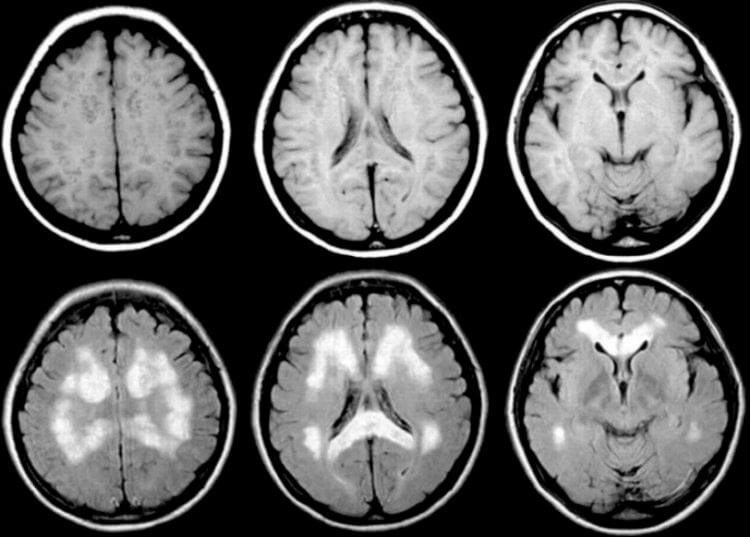

И это далеко не все, что «айтрекинг» может выведать о человеке. В этом документе также говорится о том, что по движениям глаз можно диагностировать у человека предрасположенность к тем или иным заболеваниям. В частности, там упоминается аутизм, обсессивно-компульсивное расстройство, шизофрения и болезнь Паркинсона. О последнем заболевании, кстати, я рассказывал в этой статье.

Поражение мозга при болезни Паркинсона. Сообщается, что по движениям глаз можно диагностировать даже эту болезнь